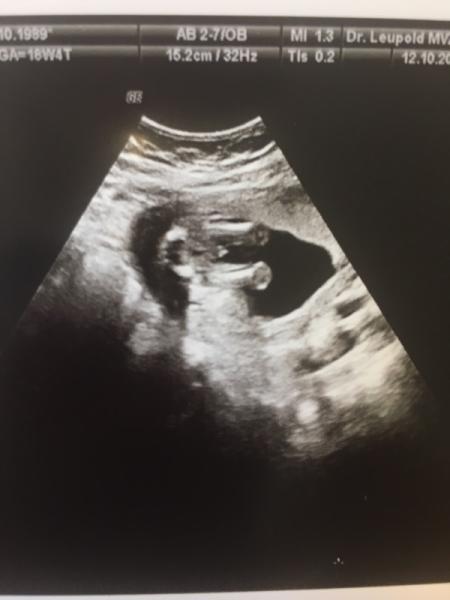

Mein Mann (und zugegebermaĂen ich auch) waren zwar ein klein wenig wehmĂŒtig, weil wir gerne unseren MĂ€dchen-Namen den wir schon bei der damaligen Schwangerschaft rausgesucht haben, vergeben wollten aber es ist natĂŒrlich trotzdem schön und wir freuen uns. So kriegt unser Sohn einen kleinen Bruder  Hier auch mal zwei Fotos

Hier auch mal zwei Fotos  Ich hoffe euch geht es auch allen gut und wĂŒnsche euch schonmal ein schönes Wochenende!